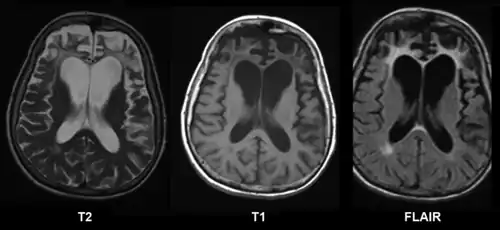

| Ressonância magnética sem contraste de uma mulher com atrofia frontal e parietal esquerda. | |

É principalmente clínico, pelo psiquiatra, neurólogo ou geriatra. Uma ressonância do cérebro pode confirmar uma atrofia frontal ou parietal maior que a esperada para a idade. O lobo frontal é associado com planejamento, personalidade e raciocínio enquanto o temporal é associado com linguagem e associação de emoções. É frequentemente confundida com uma depressão nervosa, com mal de Alzheimer ou mal de Parkinson. [5]